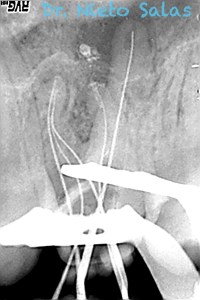

Os presento unos casos de varios molares superiores, con tres conductos mesiovestibulares con un foramen o con dos.

Una vez que tenemos medidas, obturamos los conductos: